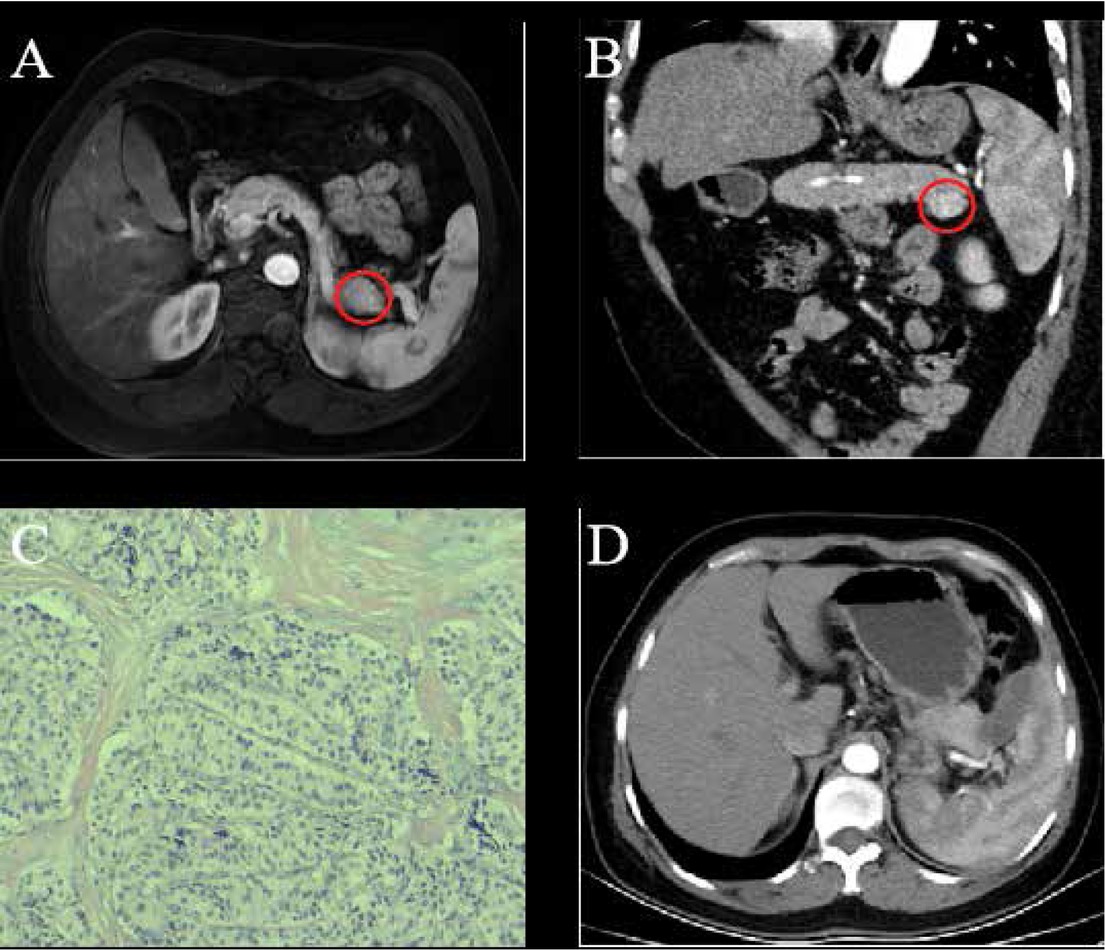

A 44-year-old female patient who had episodic hypoglycemic symptoms including sweating, palpitations and weakness for more than four years was referred to hospital. Physical examination didn’t show any abnormalities of heart, lung, kidney and other organs. Her random blood glucose was 2.4 mmol/L, fasting blood glucose was 1.7 mmol/L, glycosylated hemoglobin was 3.3% and fasting serum insulin was 372.6 mU/L. Contrast-enhanced magnetic resonance imaging (MRI) showed a round-like and well-defined lesion in the pancreatic tail with measured diameters of 18 mm × 17 mm in the arterial phase (Fig. 1 A). A coronal reconstructed CT scan showed that the tumor grew in an exophytic pattern (Fig. 1 B). The preoperative diagnosis of functioning insulinoma of the pancreatic tail was made based on the clinical symptoms, results of laboratory tests and characteristic MRI and CT imaging features.

A 44-year-old female with pathology-proven pancreatic insulinoma was treated with laparoscopic RFA. (A) Contrast-enhanced MRI showed a round-like, well-defined lesion in the pancreatic tail in the arterial phase (red cycle). (B) Coronal reconstructed CT image showed the tumor grew in an exophytic pattern (red cycle). (C) Pathology confirmed the diagnosis of pancreatic insulinoma (HE×100). (D) Contrast-enhanced CT showed no residual tumor foci and recurrent lesion with a small volume of fluid collection near the pancreatic tail.

Laparoscopic RFA was performed for the patient under general anesthesia. After the incision of the gastrocolic ligament made, an 18 mm tumor was visualized in the pancreatic tail corresponding to the tumor lesion depicted on CT and MR images. Before the RFA, a piece of tumor tissue was excised for the intraoperative pathologic examination, which confirmed the diagnosis of a benign lesion. Subsequently, a Cool-tip ACTC 2020 needle was placed in the lesion under the laparoscopic guidance with the tip of the needle being positioned in the center of the tumor. The ablation was carried with a Covidien Healthcare (Ireland, Dublin) generator with the power set at up to 40 W for the whole procedure. An abdominal drain was kept in the ablation region after the RFA procedure. The follow-up laboratory test showed the blood glucose was 7.6 - 9.8 mmol/L on the first day post the RFA procedure. No more hypoglycemia-related symptoms such as sweating, palpitation and weakness were seen. The level of fasting and random blood glucose was 5.3 mmol/L and 5.7 mmol/L respectively, the glycosylated hemoglobin was 4.3% and fasting serum insulin was 63.4 mU/L.

No pancreatic fistula occurred after the abdominal drain was withdrawn on the third postoperative day and the patient was discharged seven days later after the RFA procedure without any RFA-related complications. The pathological examination further confirmed the pre-procedural diagnosis of pancreatic insulinoma (Fig. 1 C). No recurrence of episodic hypoglycemic symptoms such as sweating, palpitation and weakness were observed in this patient during a 9-month follow-up period. Contrast-enhanced CT showed no residual tumor foci and a recurrent lesion with a small volume of fluid collection near the pancreatic tail. (Fig. 1 D).